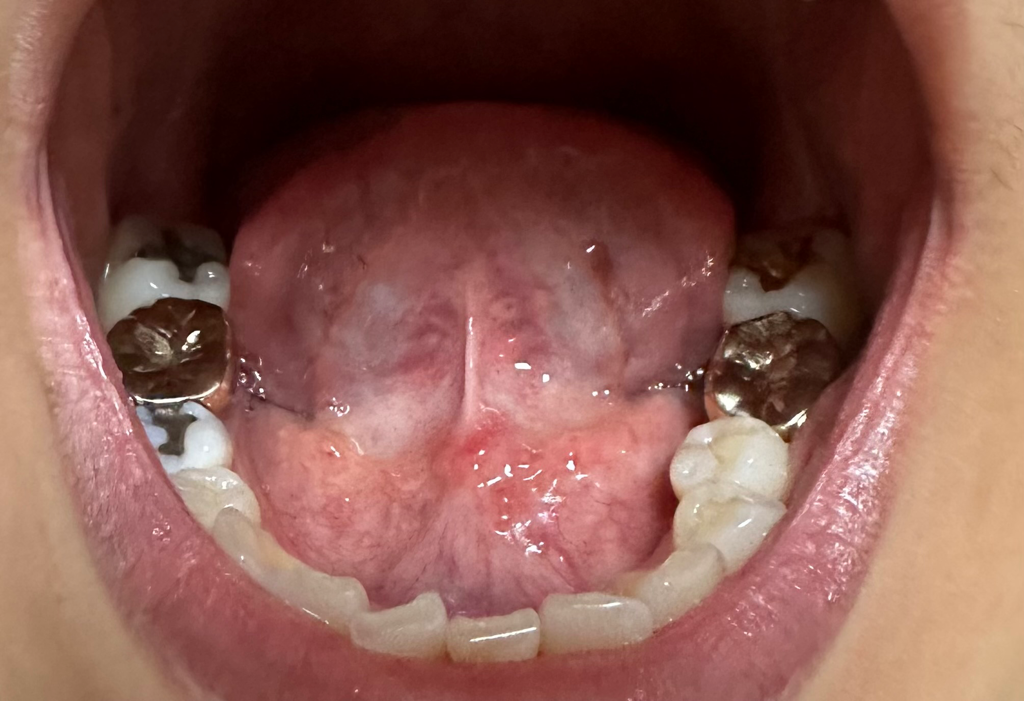

혀 밑이 좀 많이 튀어나와 있는 것 같은데 정상인가요?

어쩌다 혀 밑을 보니 살같은게 많이 튀어나와 있는 것 같은데 제 기준으로 왼쪽이 더 부풀어 있는 것 같아서요

• 3번 째 사진

특별하게 문제가 있는 상태로 보이지는 않습니다.

정사인 구조로 생각이 됩니다.

만일 특별한 증상이 없는 경우 골융기 등의 해부학적인 변형으로 돌기가 발생했을 가능성이 있겠으나, 간혹 드물게 설암인 경우에도 비슷한 양상으로 돌기가 발생할 수 있으므로 근처 치과에 가셔서 진료를 보시는 편이 안전할 것으로 사료됩니다.

모양자체는 이상소견이 있어 보이지 않습니다.

다만 비대칭성이 점차 심해지는 경우라면 이비인후과 진료를 받아보시는 것이 좋겠습니다.